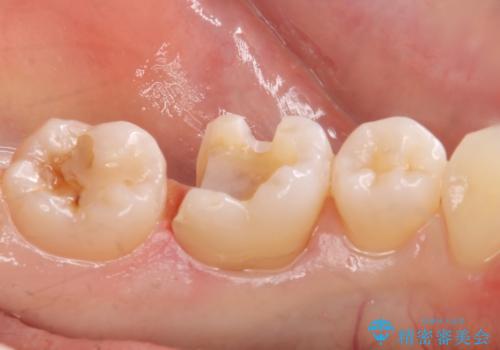

虫歯が再発していたので拡大鏡下で取り切った後、e-maxインレーにて治療しました。

また、一番奥の歯も古い樹脂の治療がされていたため虫歯の予防のために樹脂を取り除き、う蝕がないことを確認してe-maxインレーで治療しました。

- e-maxインレー 7.7万円 ×2本費用は治療当時の料金となります

e-max(セラミック)は歯質との隙間が出来にくく虫歯の再発のリスクが低くなります。